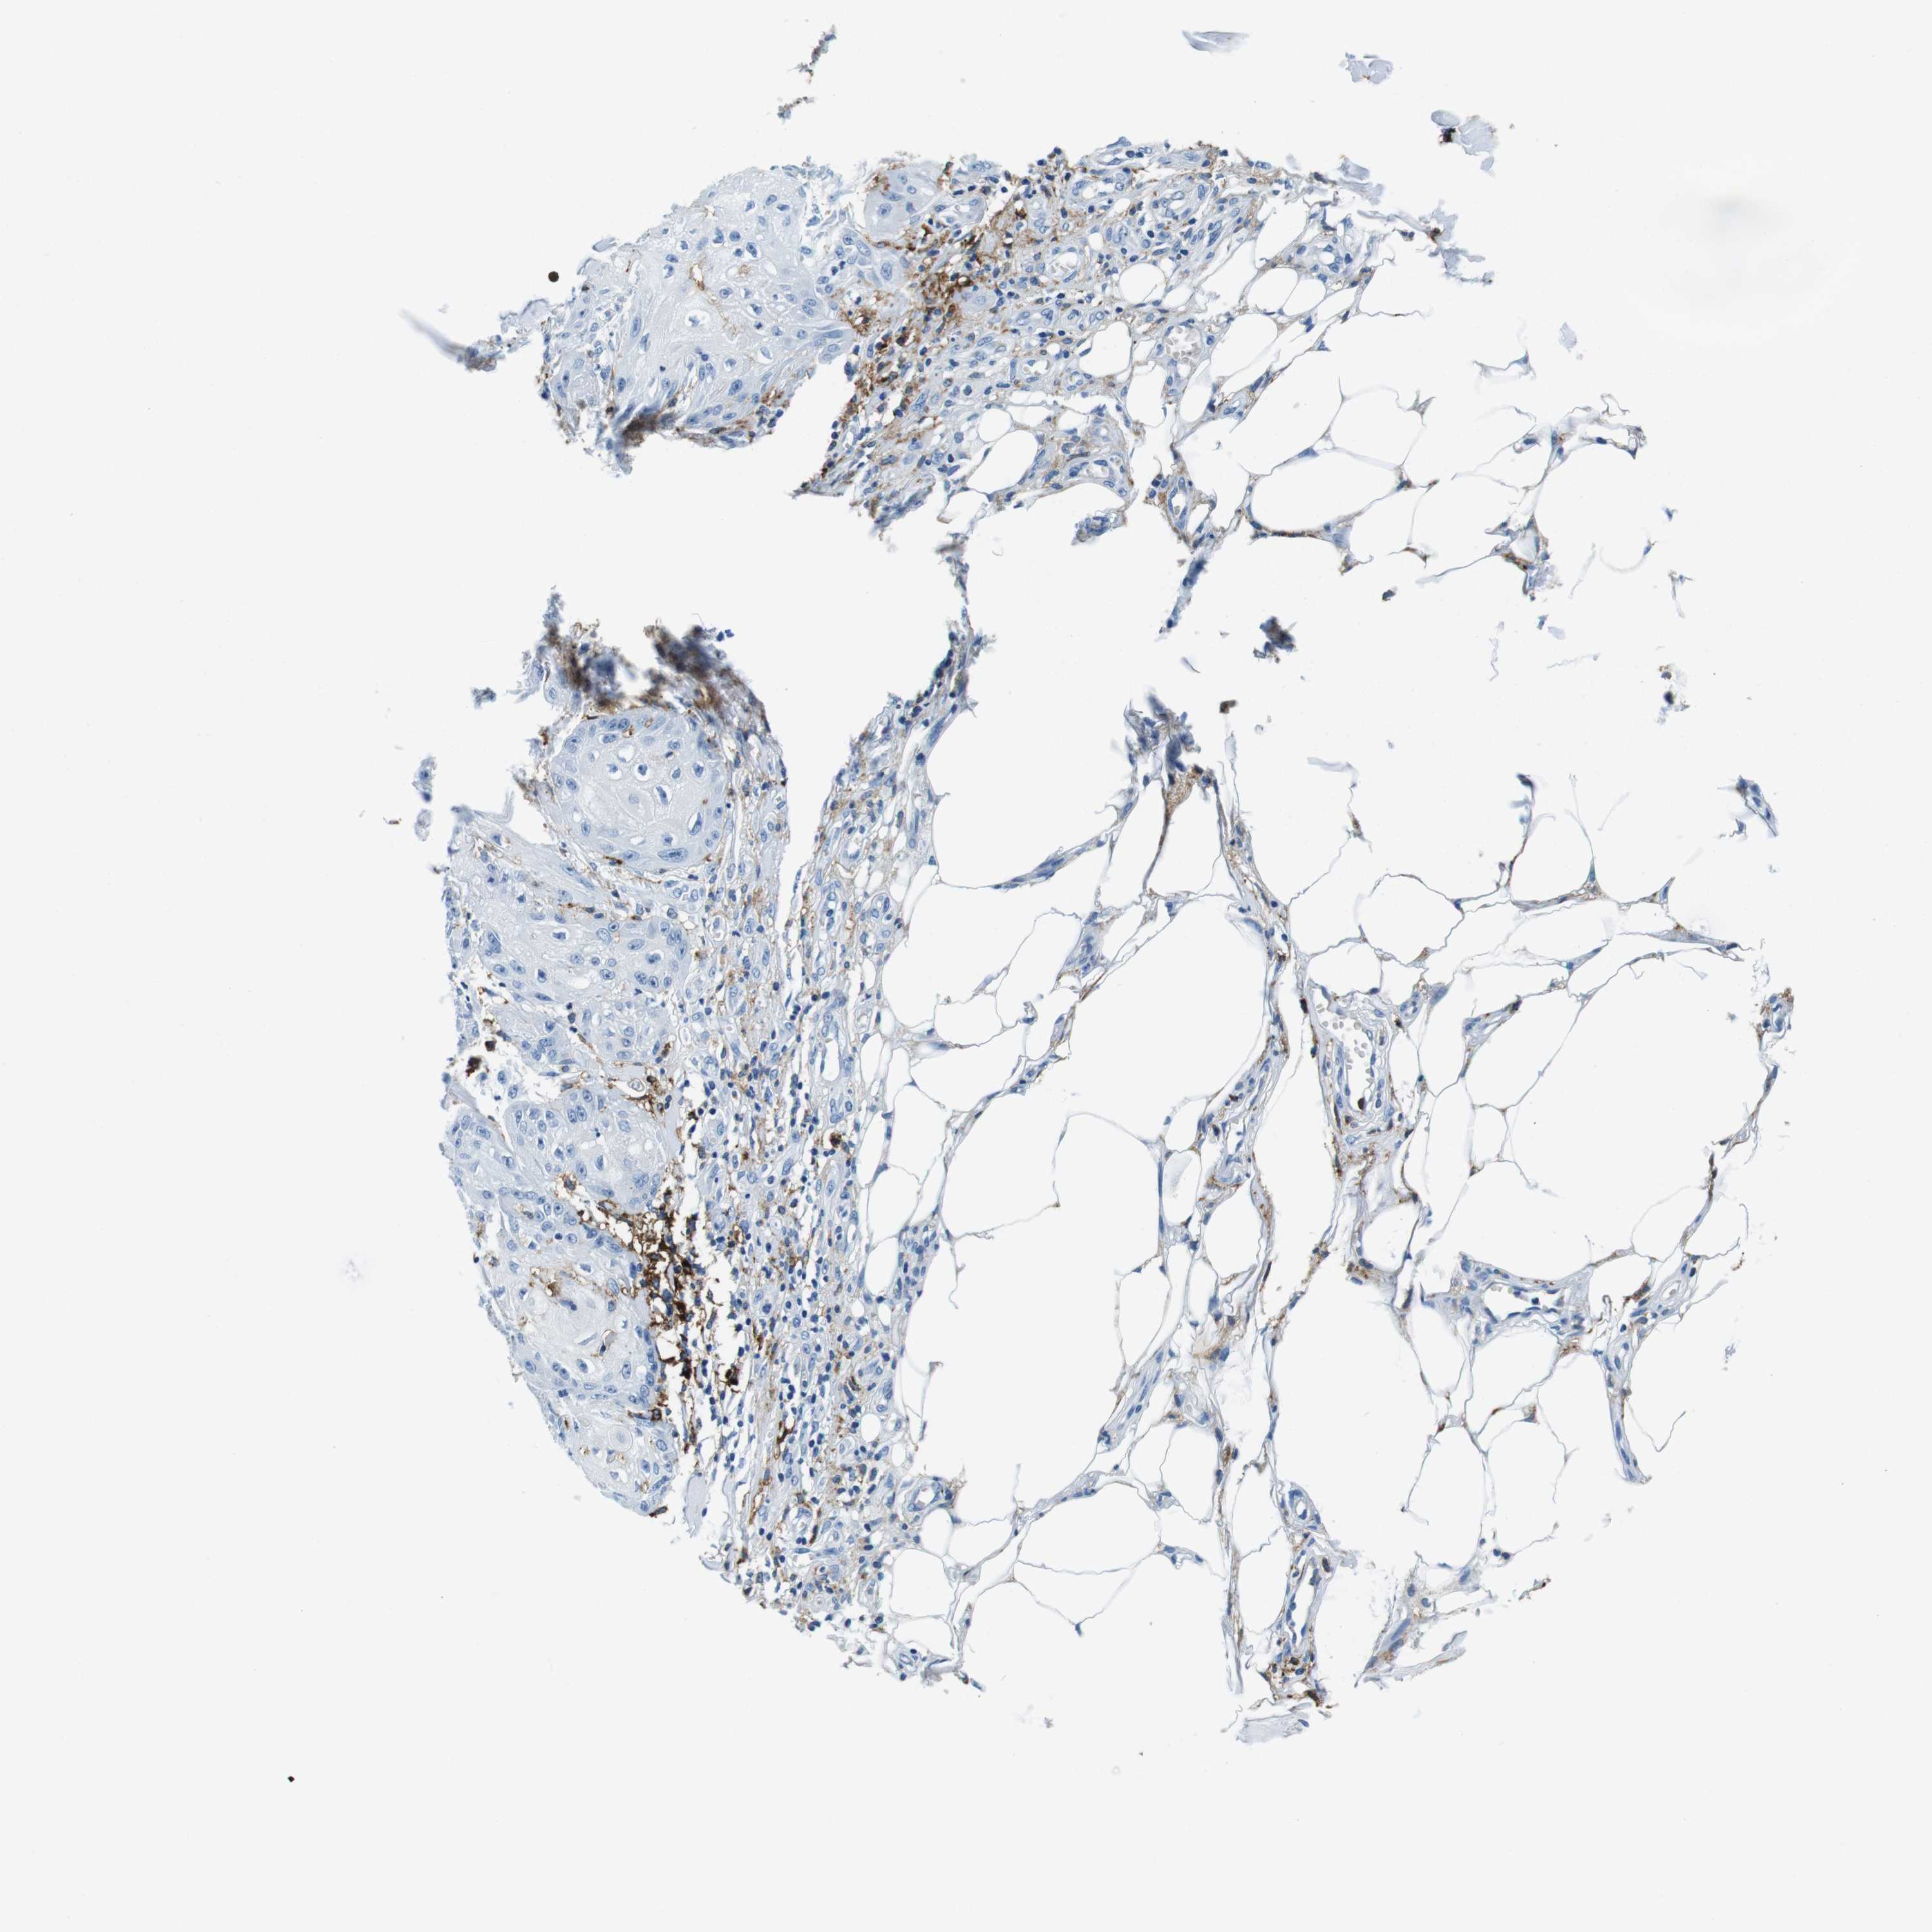

SKIN CANCER - Protein expressioni

A mouse-over function shows sample information and annotation data. Click on an image to view it in a full screen mode. Samples can be filtered based on level of antibody staining by selecting one or several of the following categories: high, medium, low and not detected. The assay and annotation is described here.

Each image is clickable and will lead to virtual microscopy that enables deeper exploration of all samples and also displays staining intensity scores, fraction scores and subcellular localization as well as patient and tissue information for each sample.

Antibody HPA043151

Basal cell carcinoma

Adnexal tumor, benign